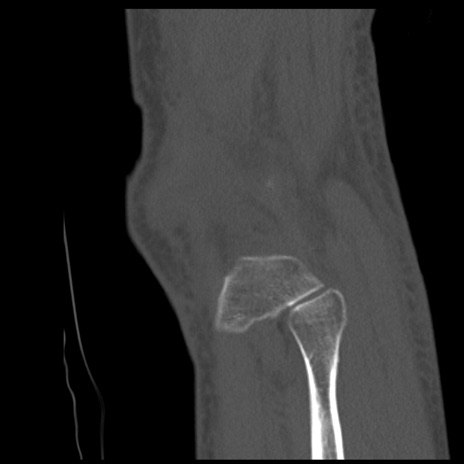

症例28 右膝関節CT(矢状断像)

右膝関節CT